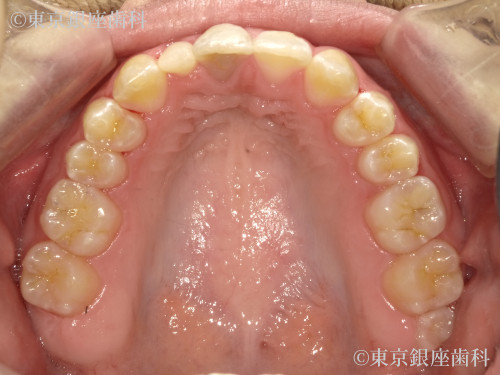

Before

20代 女性

疾患 矯正

施術内容 矯正

治療期間 1年1ヶ月 費用 90万円(税込)

インビザライン:コンプリヘンシブパッケージ